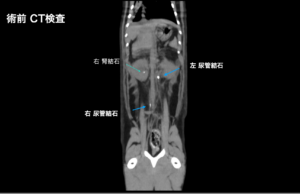

腹部超音波検査およびX線検査により、右遠位尿管および左近位尿管に結石を確認し、両側腎盂拡張を伴う尿管閉塞が認められた。

• 右側:尿管膀胱新吻合術(ureteroneocystostomy)を実施し、術後の尿流確保を目的として腎瘻チューブ設置

• 左側:近位尿管切開術により結石を摘出